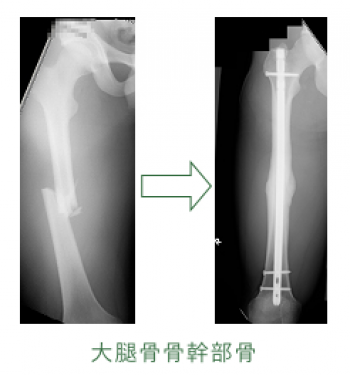

大腿骨骨幹部骨折

大腿骨骨幹部骨折は、比較的頻度が高い。

20〜50歳の青壮年に多発するが小児もまれではない。

骨幹部骨折は常に強力な外力により発生するため軟部組織損傷も高度で、開放性骨折になりやすい。